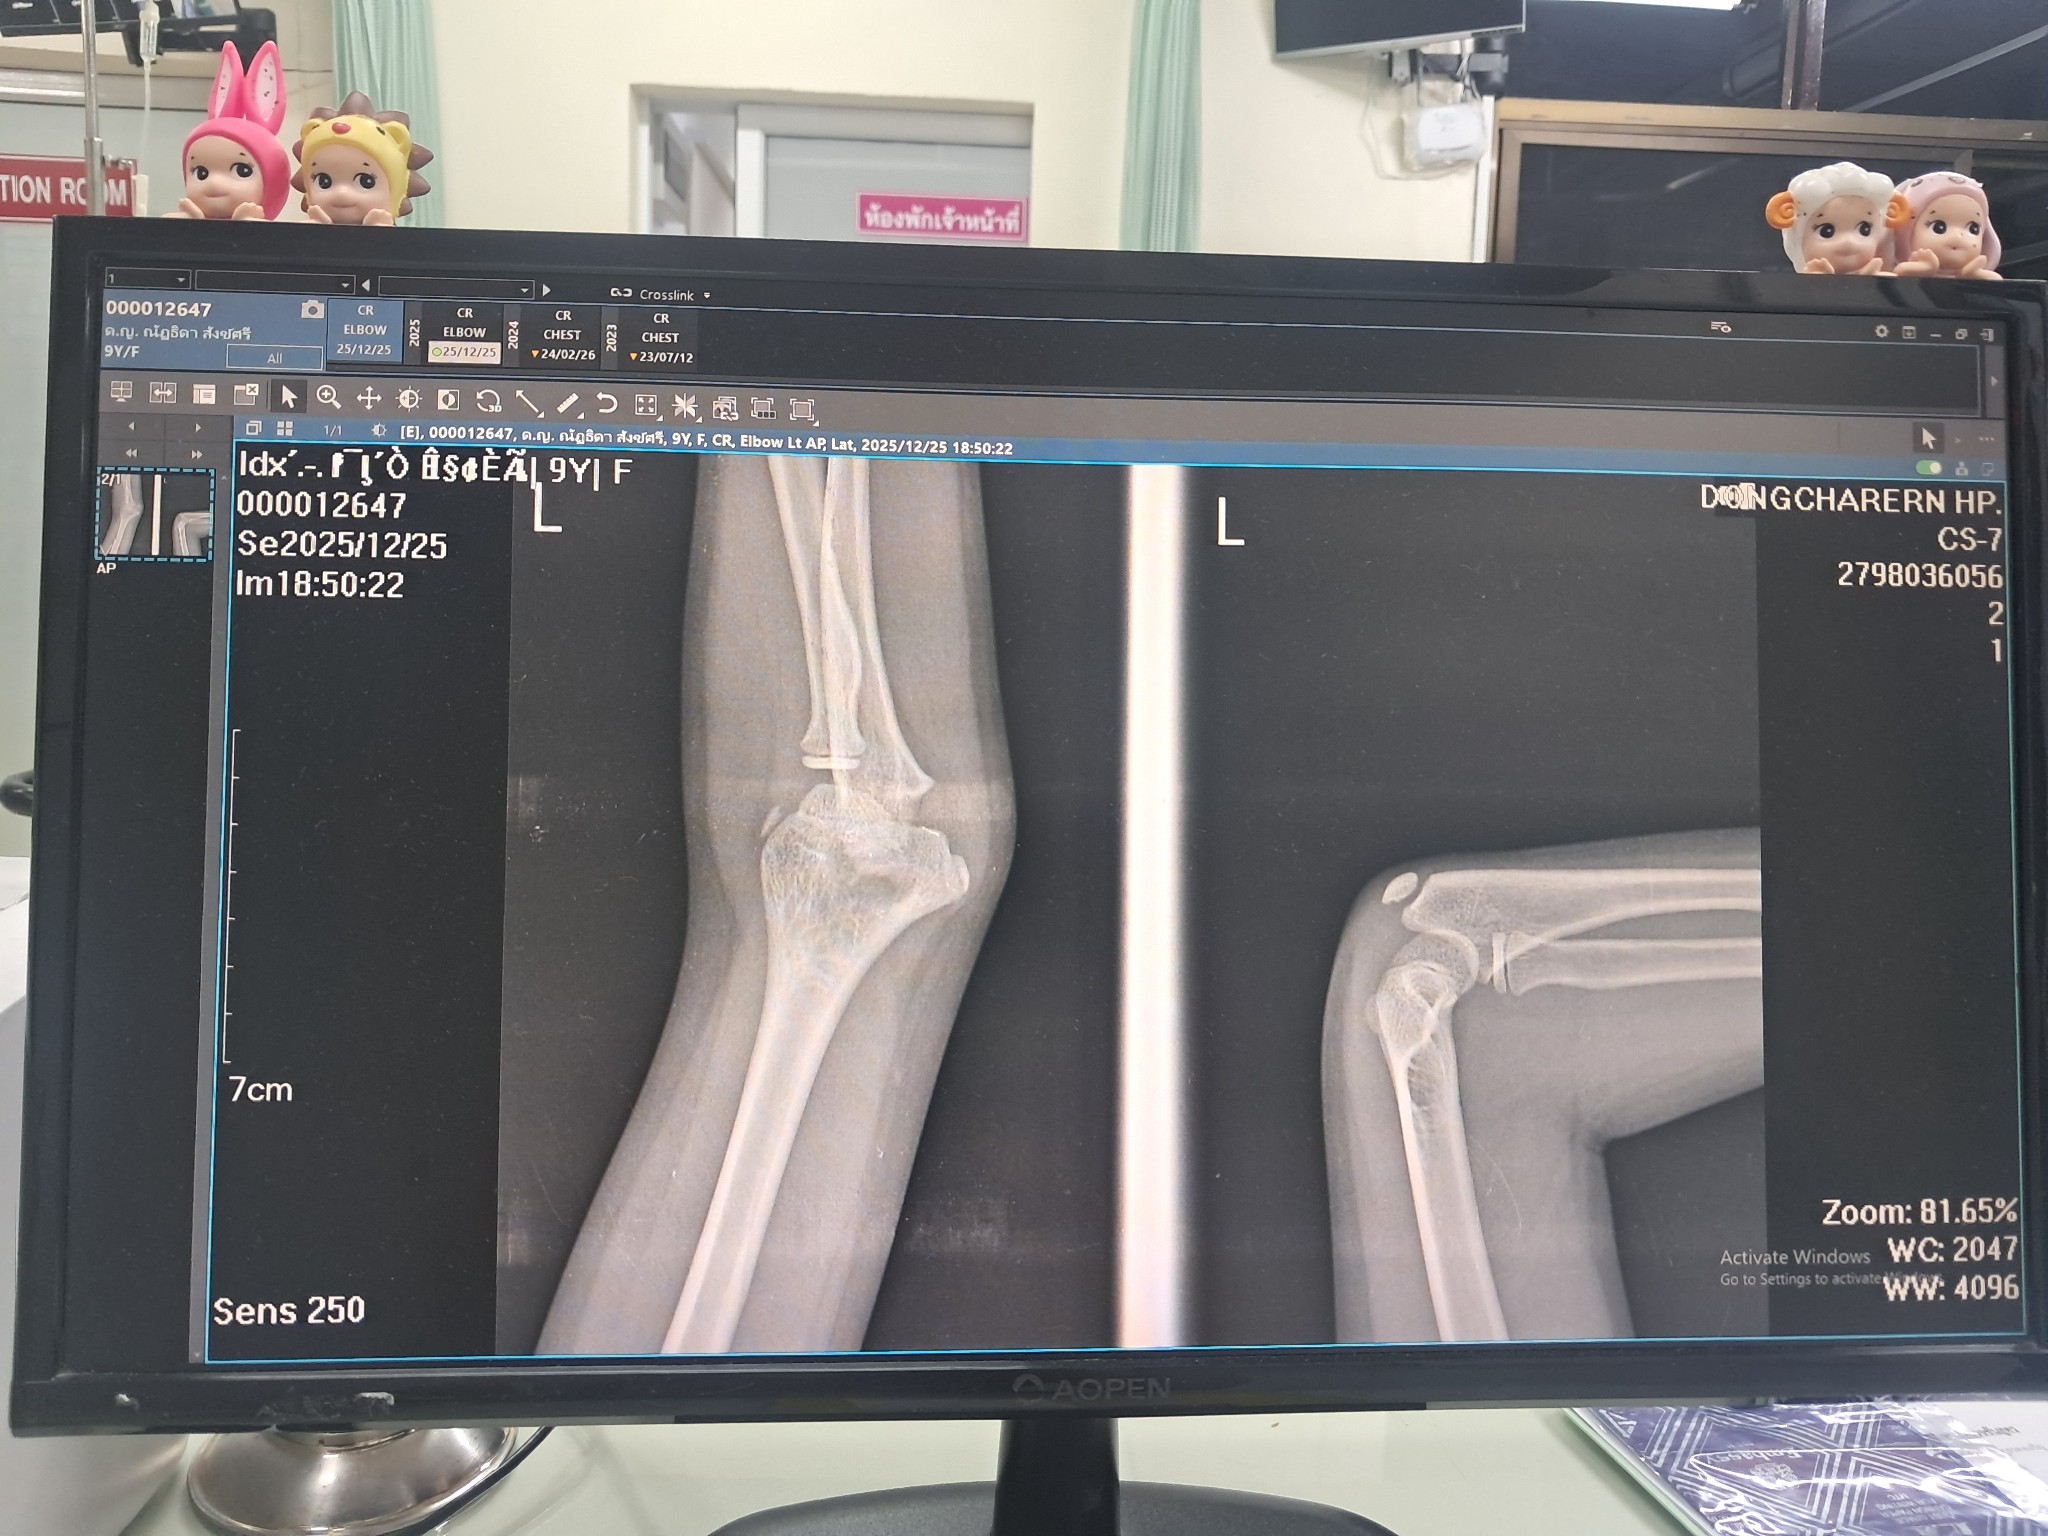

ในภาพมีการหักของกระดูกไหมคะ

สอบถามค่ะ ภาพเอกซเรย์ จากกระดูก คือมีการหักของกระดูกไหมคะ ภาพขวามือค่ะ